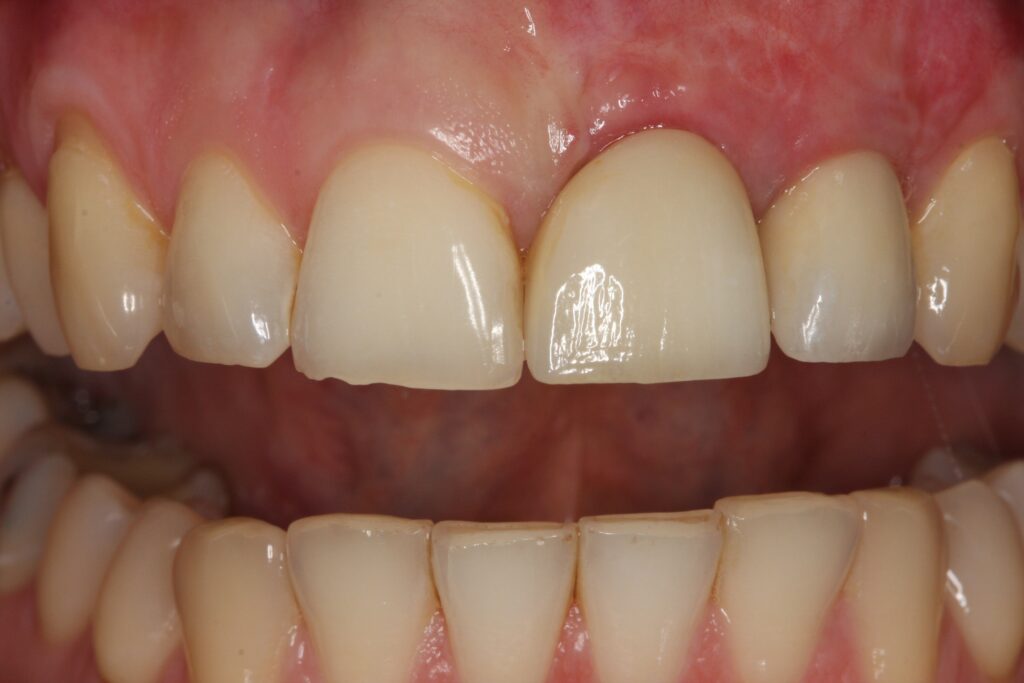

Nachdem die gewünschte Stabilität des Kieferknochens erreicht wurde, konnte Prof. Dr. Olze mit dem Setzen der Implantate beginnen. Um langfristig für Stabilität und Ästhetik zu sorgen und um einen erneuten Eingriff vermeiden zu können, wählte er in Absprache mit der Patientin hochwertige ANKYLOS®- Implantate und Zahnersatzkomponenten von Dentsply Sirona. Diese Versorgungslösung ermöglicht eine lange Haltbarkeit und mechanische Stabilität. Auch auf ästhetischer Ebene überzeugt diese qualitativ hochwertige Lösung. Hiermit ist sichergestellt, dass die Patientin auch nach Jahrzehnten noch unbeschwert lachen und abbeißen kann. Durch die innovative Knochenaufbaumethode und die nachhaltig konzipierten Implantatkomponenten wird einem späteren Knochenabbau entgegengewirkt und das Gewebe bleibt anhaltend stabil und gesund.

Ihr Zahnarzt Berlin Mitte, Prof. Dr. Olze & Kollegen, freut sich mittlerweile über eine große Anzahl von Patientenfällen, bei welchen ein schönes, strahlendes Lächeln wiederhergestellt werden konnte. Egal wie kompliziert Ihr Fall ist, wir kümmern uns sehr gern mit viel Erfahrung, Fachkompetenz und Einfühlungsvermögen um Sie! Auch wenn Sie an anderer Stelle negative Erfahrungen gesammelt und bei Vorbehandlern zahlreiche vergebliche Eingriffe im Vorfeld erlebt haben, können Sie gemeinsam mit uns Ihr Ziel erreichen und mit gesunden, schönen Zähnen Ihre Lebensqualität zurück erlangen. Wir unterstützen Sie gern und machen scheinbar Unmögliches möglich.